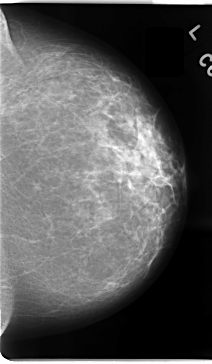

C_0094_1.LEFT_CC

LEFT_CC LINES 4720 PIXELS_PER_LINE 2744 BITS_PER_PIXEL 12 RESOLUTION 50 NON_OVERLAY